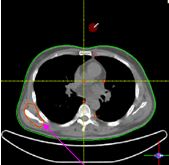

Chúng tôi đã tiến hành ghi hình PET/CT toàn thân cho bệnh nhân và dùng hình ảnh PET/CT để lập kế hoạch xạ trị cho bệnh nhân.

Trên hình ảnh CT rất khó để nhận diện tổn thương di căn xương bả vai phải, một số cung xương sườn của bệnh nhân cũng như tổn thương di căn cột sống. Tuy nhiên với việc kết hợp hình ảnh PET và CT, việc đánh giá tổn thương di căn xương để tiến hành lập kế hoạch xạ trị trở nên chính xác hơn nhiều.

Cũng như các phương pháp điều trị khác, xạ trị cũng có những ưu điểm và nhược điểm riêng. Để tiêu diệt các tế bào ung thư thì các tổ chức lành xung quanh khối u ít nhiều cũng bị ảnh hưởng, đặc biệt khi xạ trị vào vùng đầu mặt cổ. Do vậy việc xác định rõ mức độ xâm lấn của khối u và hạch rất quan trọng. Việc lập kế hoạch dựa trên hình ảnh PET/CT cho phép đánh giá được mức độ xâm lấn của tổ chức ung thư vào tổ chức lành, từ đó giúp cho bác sỹ xạ trị chỉ định được liều lượng xạ trị và lập kế hoạch xạ trị được tốt hơn.

Tại Việt Nam với hệ thống máy gia tốc tuyến tính cho phép lập kế hoạch xạ trị theo không gian ba chiều (3D conformal radiotherapy) và xạ trị điều biến liều (IMRT, intensity modulated radiation therapy), trong đó phương pháp xạ trị điều biến liều giúp lập kế hoạch xạ trị hoàn hảo hơn với việc liều lượng xạ trị được tập trung tốt hơn vào vùng u mà lại giảm thiểu tối đa liều bức xạ vào tổ chức lành xung quanh khối u. Việc kết hợp lập kế hoạch xạ trị dựa trên hình ảnh PET/CT và xạ trị điều biến liều IMRT sẽ giúp mang lại kết quả điều trị xạ trị tốt nhất tại Việt Nam hiện nay.